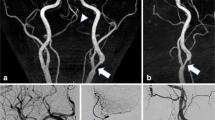

For the patient with intracranial atherosclerosis, the 2D DSA showed limited delineation of LSAs, especially for branches, whereas CS TOF delineates clear outlines and origins of LSAs, and the distal branches (Fig. 5). Although 3D DSA has a better delineation of LSAs than 2D DSA, the visual depiction of distal LSA branches is still inferior to that of CS TOF (red arrows, Fig. 5).

Comparisons of LSA between CS TOF and DSA in a patient with symptomatic intracranial arterial stenosis on M1 segment of right MCA. Both DSA images (2D and 3D) showed inferior visual delineation of LSAs compared with CS TOF. CS, compressed sensing; DSA, digital subtraction angiography; LSA, lenticulostriate artery; MCA, middle cerebral artery; TOF, time-of-flight

DSA is commonly considered the “gold standard” for LSA visualization. Kang et al suggested that the distribution of LSAs can be visualized by DSA with a 3D reconstruction of rotational angiography [28]. Our initial results showed that CS TOF has better outlines and delineations of LSA branches (Fig. 5) compared with both 2D and 3D DSA. In addition, it is challenging to track LSA branches on routine 2D DSA due to the faint filling of LSA branches and the disturbance of other vascular branches. Moreover, DSA is invasive and requires intra-arterial catheterization, which may carry substantial risks of morbidity or mortality [29]. Thus, the DSA technique might not be the method of choice for screening healthy individuals or asymptomatic patients if the subject appears to have risk factors for stroke. Whether CS TOF can replace DSA and become the gold standard of LSA imaging needs to be further verified in more settings.